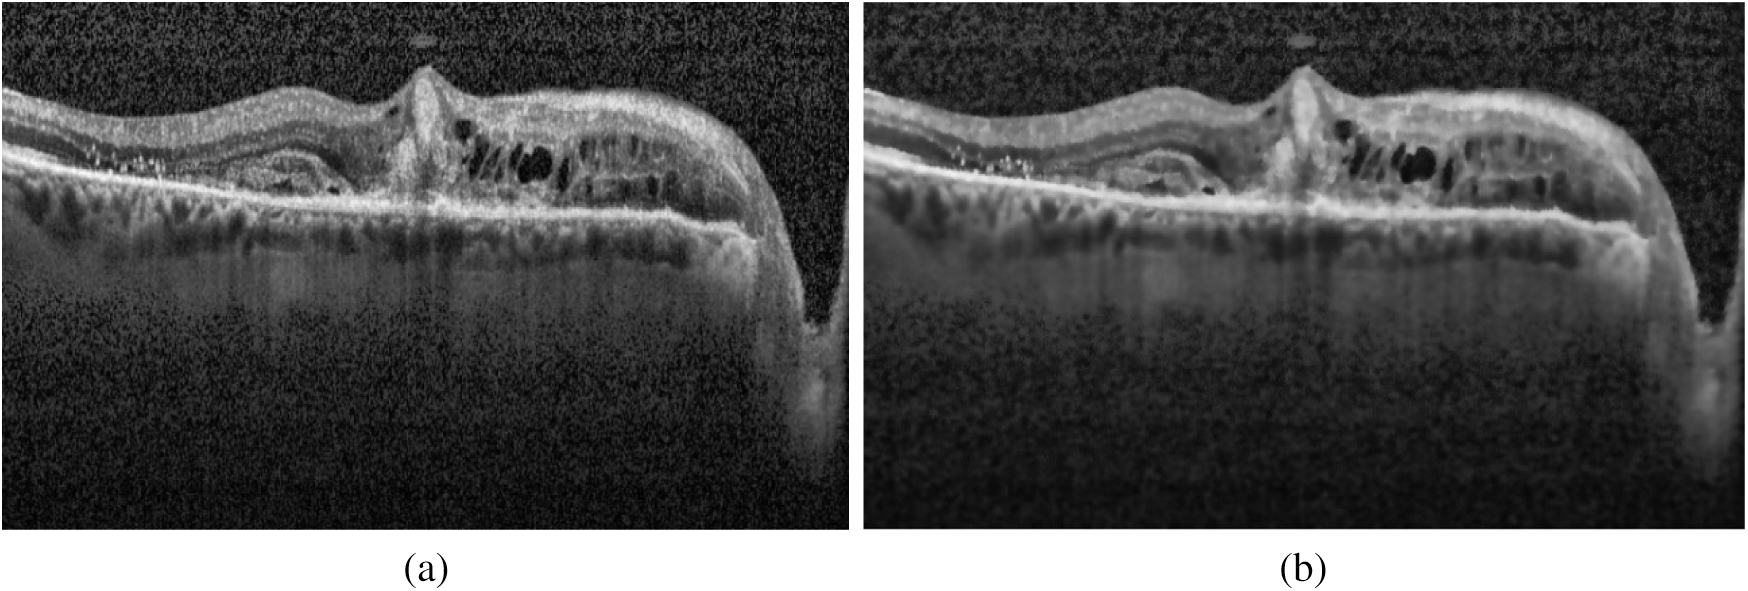

It is an image enhancement process for better visualization. CLAHE [26] is a digital image processing technique in which the image visibility is improved by enhancing the contrast of local regions of images. The OCT images were highly saturated as can be seen in the following Fig. 3(a). CLAHE works on small patches of the image called tiles. The contrast improved tiles are combined using the bilinear interpolation to reduce the effect of artificial boundaries.

Figure 3: Image preprocessing step: (a) Histogram of the original image; (b) Effect of applying CLAHE

After normalization of saturated images, the denoising was performed on the highly noisy OCT images. To retain the salient features of the image, the bilateral filter [27] has been employed. It is a non-iterative, non-linear, and local algorithm that works at both the range and domain of the image. It can distinguish the resemblance of gray levels, and the geometric intimacy of the neighboring pixels. The effect of image denoising is shown in Fig. 4.

Figure 4: Effect of applying the bilateral filter for removing noise: (a) Original image; (b) Denoised image